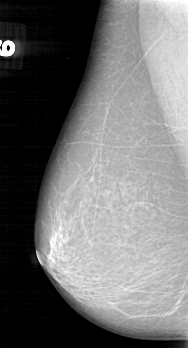

D_4042_1.RIGHT_MLO

RIGHT_CC LINES 5386 PIXELS_PER_LINE 3001 BITS_PER_PIXEL 12 RESOLUTION 43.5 NON_OVERLAY

RIGHT_MLO LINES 5206 PIXELS_PER_LINE 2806 BITS_PER_PIXEL 12 RESOLUTION 43.5 NON_OVERLAY